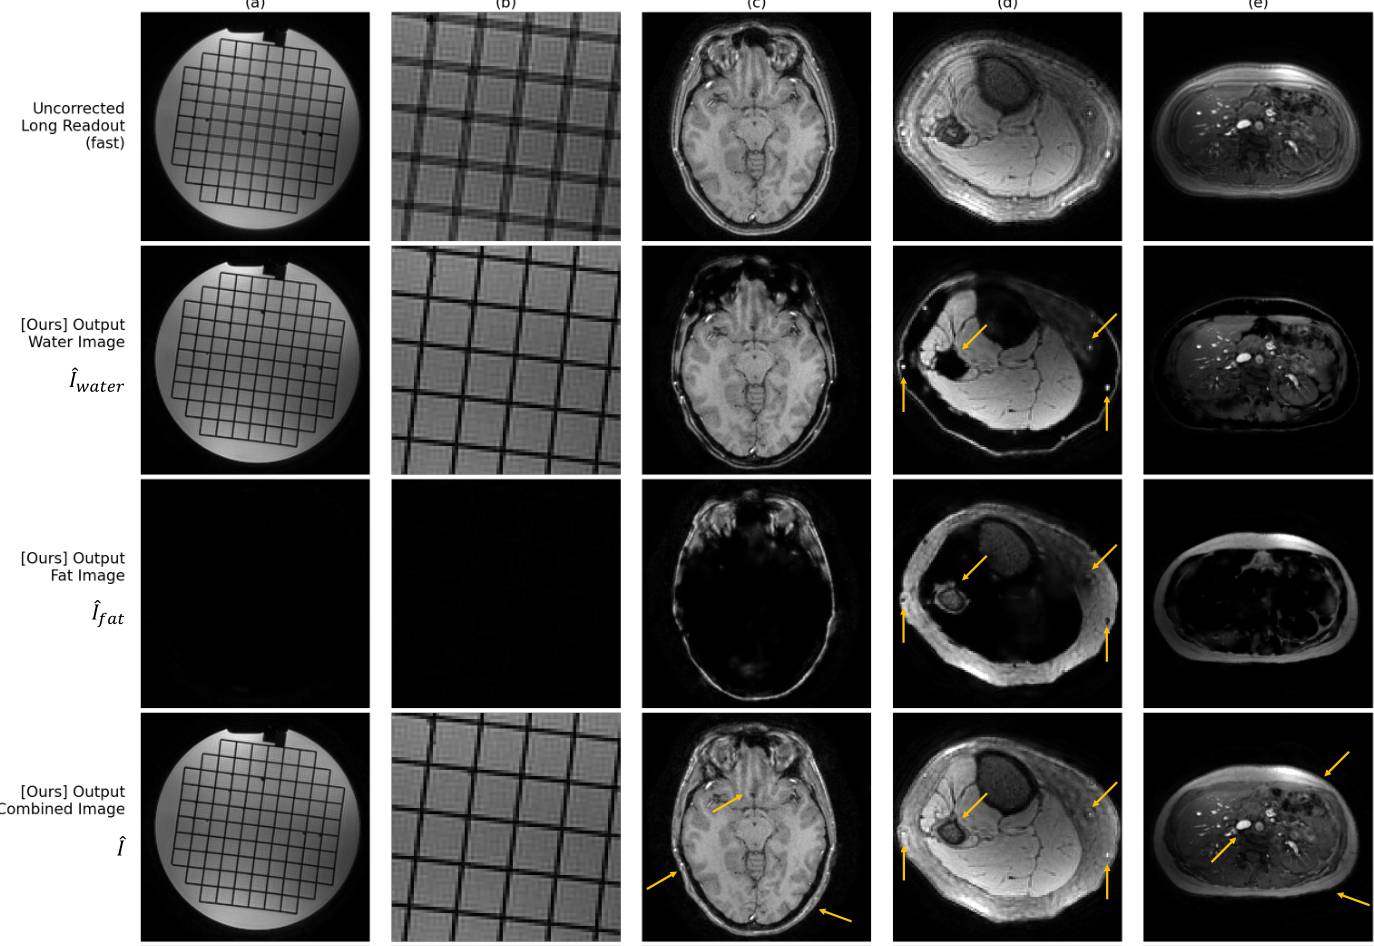

- Fat/water separation: Enabling explicit separation of fat and water signals within each voxel, while also producing combined artifact-corrected images

- Generalizability across anatomies: Demonstrating robust correction of off-resonance artifacts on phantom, brain, knee, and abdominal in-vivo data, without retraining for specific anatomies or contrasts